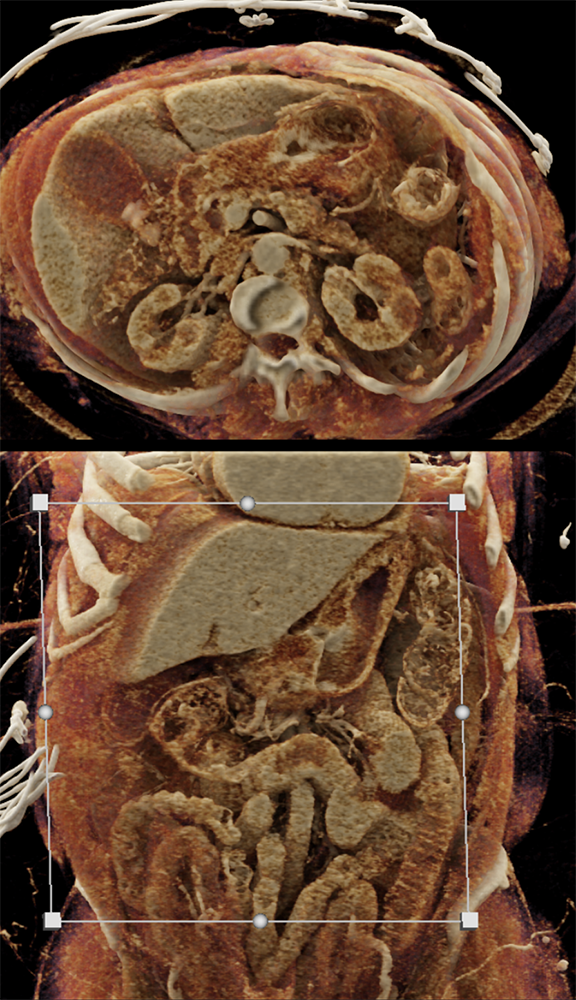

Gastric Ulcer with Perforation ![]() |

![]() |

“Gastritis can be secondary to many etiologies including infection, systemic illness such as trauma or burns, and autoimmune disease. Peptic ulcer disease is most commonly caused by Helicobacter Pylori infection and chronic NSAID use . The most common sites for ulcer formation are the gastric antrum/pylorus and proximal duodenum. The resultant edema and fibrosis around the ulcer site can cause narrowing and eventual obstruction of the gastric outlet [9]. Prior to the widespread use of H2 blockers and proton pump inhibitors, peptic ulcer disease was the most common cause of gastric outlet obstruction, however in the era of H2 blockers, outlet obstruction now predicts malignancy. While endoscopy is the modality of choice for diagnosing gastritis, CT is often performed first particularly in the setting of acute abdominal pain.” Imaging of acute gastric emergencies: a case-based review Jetty S et al. Clinical Imaging 72 (2021) 97–113 |

“On imaging, it can be difficult to distinguish benign peptic ulcer disease from malignant causes of gastric outlet obstruction and biopsy is required for confirmation. Peptic ulcers can perforate and should be recognized on imaging.” Imaging of acute gastric emergencies: a case-based review Jetty S et al. Clinical Imaging 72 (2021) 97–113 |